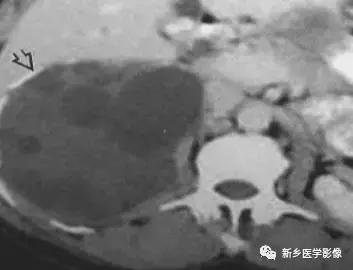

13、肾脏肿瘤

主要包括合并钙化的常见肿瘤或肿瘤样病变,如:肾囊肿,肾细胞癌,多房囊性肾瘤,多囊肝多囊肾囊壁钙化,肾脏结核,肾脏钙乳症。